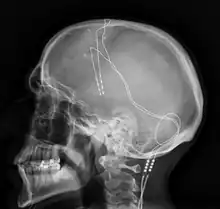

Radiographie latérale du crâne d'un homme de 42 ans, atteint de TOC sévère, traité par stimulation cérébrale profonde en 2013.

La stimulation cérébrale profonde consiste à implanter des électrodes au niveau des ganglions de la base. Elle a montré des résultats prometteurs[53],[62]. Ce traitement est limité aux formes les plus sévères de la maladie du fait de son caractère invasif et du risque d'infection liée à l'opération.